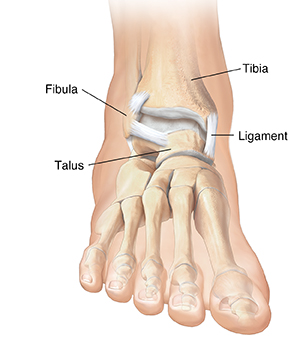

The ankle is formed by bones in the lower leg (tibia and fibula) and the bone on top of the foot (talus). When you have a fracture of the ankle, it means that 1 or more of the bones in the ankle are broken. The bone may be cracked, broken into 2 or more pieces, or even shattered. The pieces of bone may be lined up or they may have moved out of place. Sometimes, the bone may break through the skin. Nearby ligaments may also be damaged. Depending on how badly the bone is broken, healing may take a few months or longer.